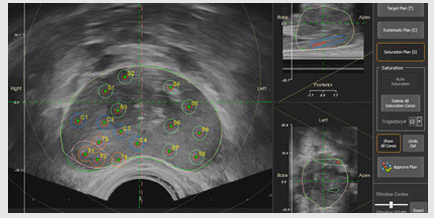

图像融合技术:Mona Lisa 2.0系统具备MRI-超声图像融合能力,能够将MRI和实时超声图像进行弹性融合,提供3D可视化,帮助医生更精准地定位目标区域。

双锥针轨迹技术:该系统采用创新的双锥针轨迹技术,通过相同的进针点提取多个活检核心,最大限度地减少耻骨弓的干扰,实现完全的前列腺覆盖。

- 灵活的穿刺规划:通过智能软件进行手术规划和交互调整,医生可以在术前制定个性化的穿刺计划,并在术中进行实时调整。

- 自定义活检:用户界面允许混合和匹配三种活检计划选项,以创建自定义活检计划。